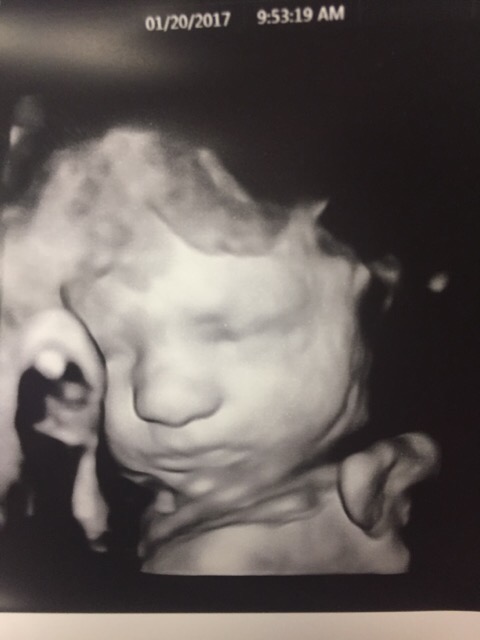

Anyone else think this kiddo is going to look like his dad? That nose looks so similar!